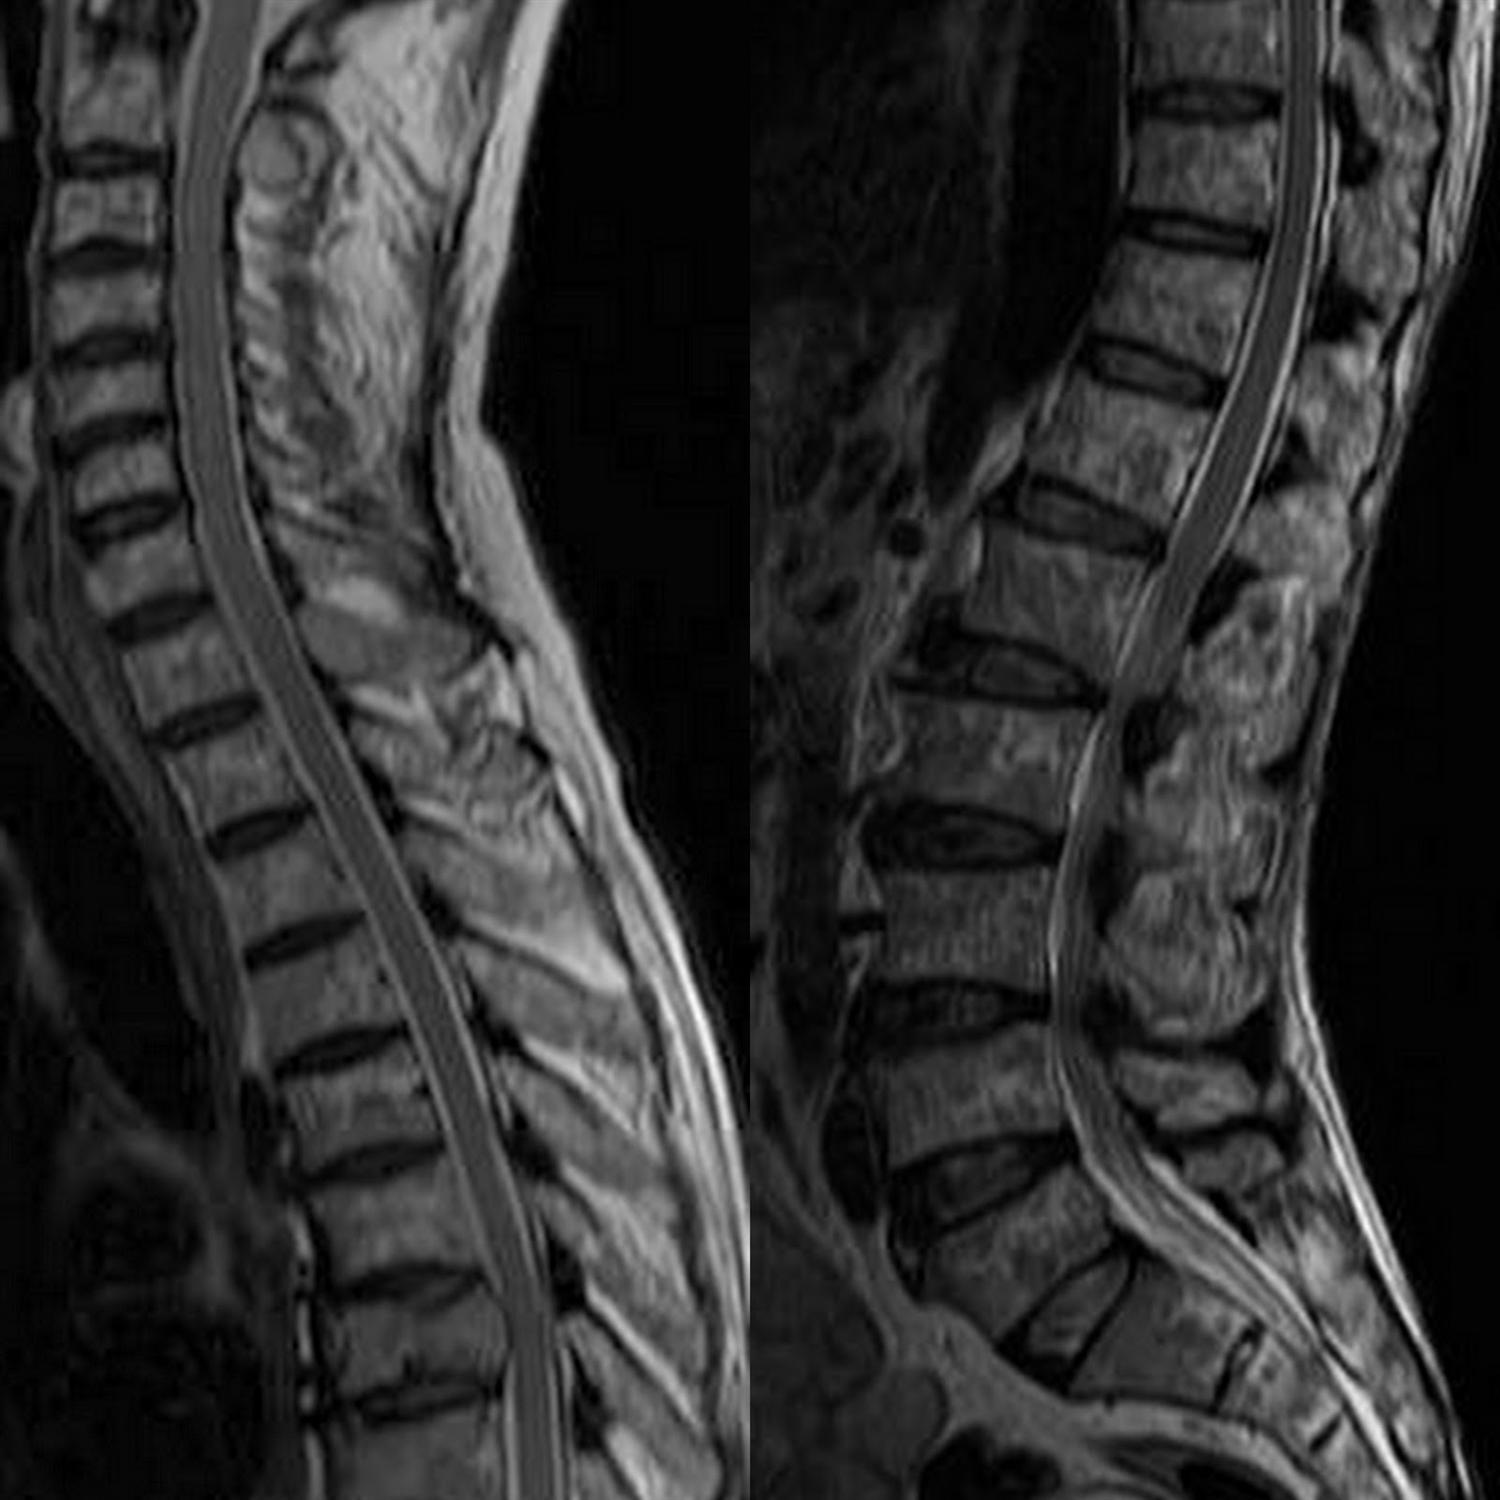

MRI examination showing (A) a dumbbellshaped lesion with demonstration Salt And Pepper Appearance Ct “salt” appearance secondary to subacute hemorrhage. In this case, a young male patient with hypovitaminosis d and secondary hyperparathyroidism, radiological features. “pepper” appearance due to flow voids. All contusions are hemorrhagic, but the extent of edema versus hemorrhage in an. Salt and pepper appearance of the skull (sometimes called, pepper pot skull), bone cysts, brown tumors of long bones, and. Salt And Pepper Appearance Ct.